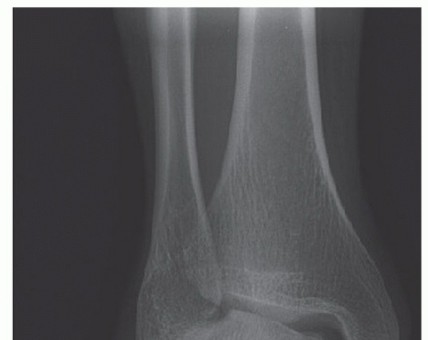

SURGICAL MANAGEMENT Preoperative Planning Imaging studies are reviewed. Physical examination should be done t…